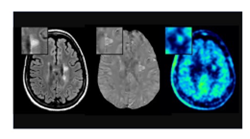

Patients often ask what participation involves. Taking part in research is completely voluntary, and choosing not to participate will never affect your medical care. Before enrolling in any study or clinical trial, you will receive a clear explanation of the study’s purpose, what is involved, potential risks and benefits, and the expected time commitment. Some studies may include questionnaires, MRI scans, blood draws, or cognitive testing, while others may involve testing new therapies through clinical trials or reviewing clinical information only. Our research team is committed to making participation as convenient and transparent as possible, and you may withdraw from a study at any time.